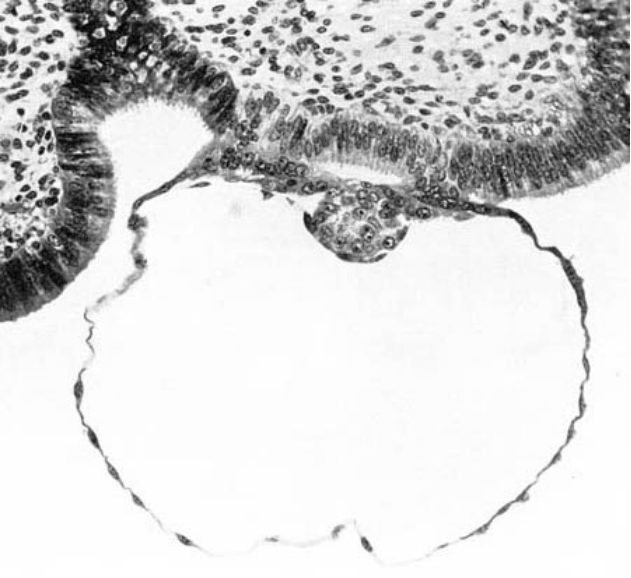

胚泡形成光镜图:

排卵、受精与卵裂过程: 胚泡附着于子宫内膜上皮光镜图:

胚泡植入子宫内膜光镜图